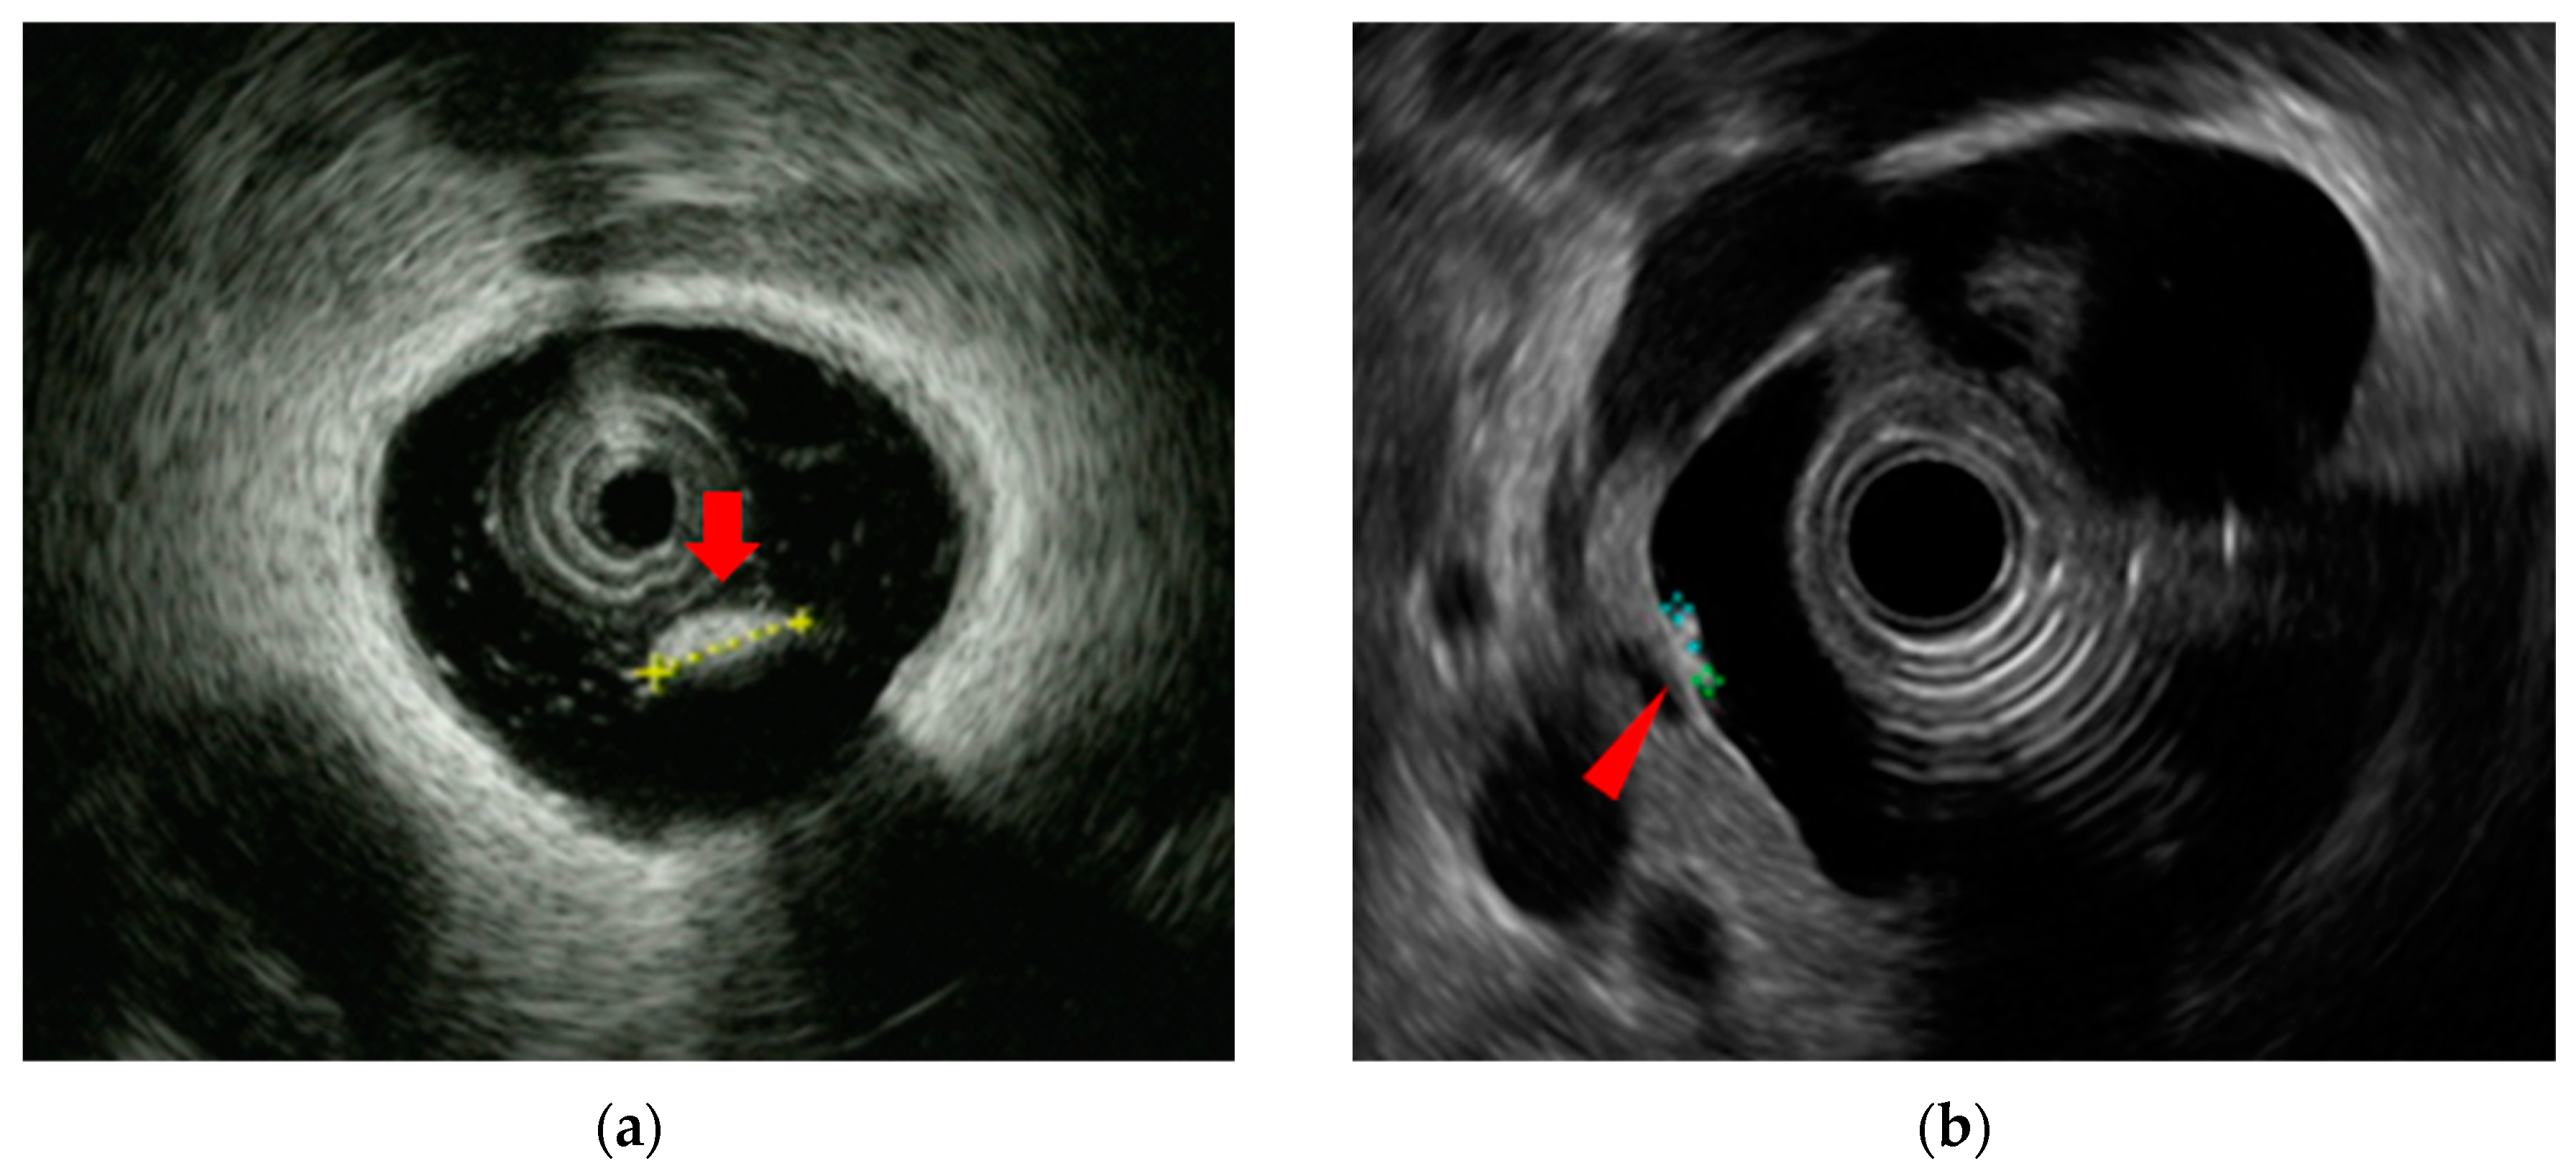

- Naitoh, I.; Nakazawa, T.; Ohara, H.; Ando, T.; Hayashi, K.; Tanaka, H.; Okumura, F.; Takahashi, S.; Joh, T. Endoscopic transpapillary intraductal ultrasonography and biopsy in the diagnosis of IgG4-related sclerosing cholangitis. J. Gastroenterol. 2009, 44, 1147–1155. [Google Scholar] [CrossRef]

- Naitoh, I.; Nakazawa, T.; Hayashi, K.; Miyabe, K.; Shimizu, S.; Kondo, H.; Nishi, Y.; Yoshida, M.; Umemura, S.; Hori, Y.; et al. Comparison of intraductal ultrasonography findings between primary sclerosing cholangitis and IgG4-related sclerosing cholangitis. J. Gastroenterol. Hepatol. 2015, 30, 1104–1109. [Google Scholar] [CrossRef]

- Naitoh, I.; Nakazawa, T. Classification and Diagnostic Criteria for IgG4-Related Sclerosing Cholangitis. Gut Liver 2022, 16, 28–36. [Google Scholar] [CrossRef]